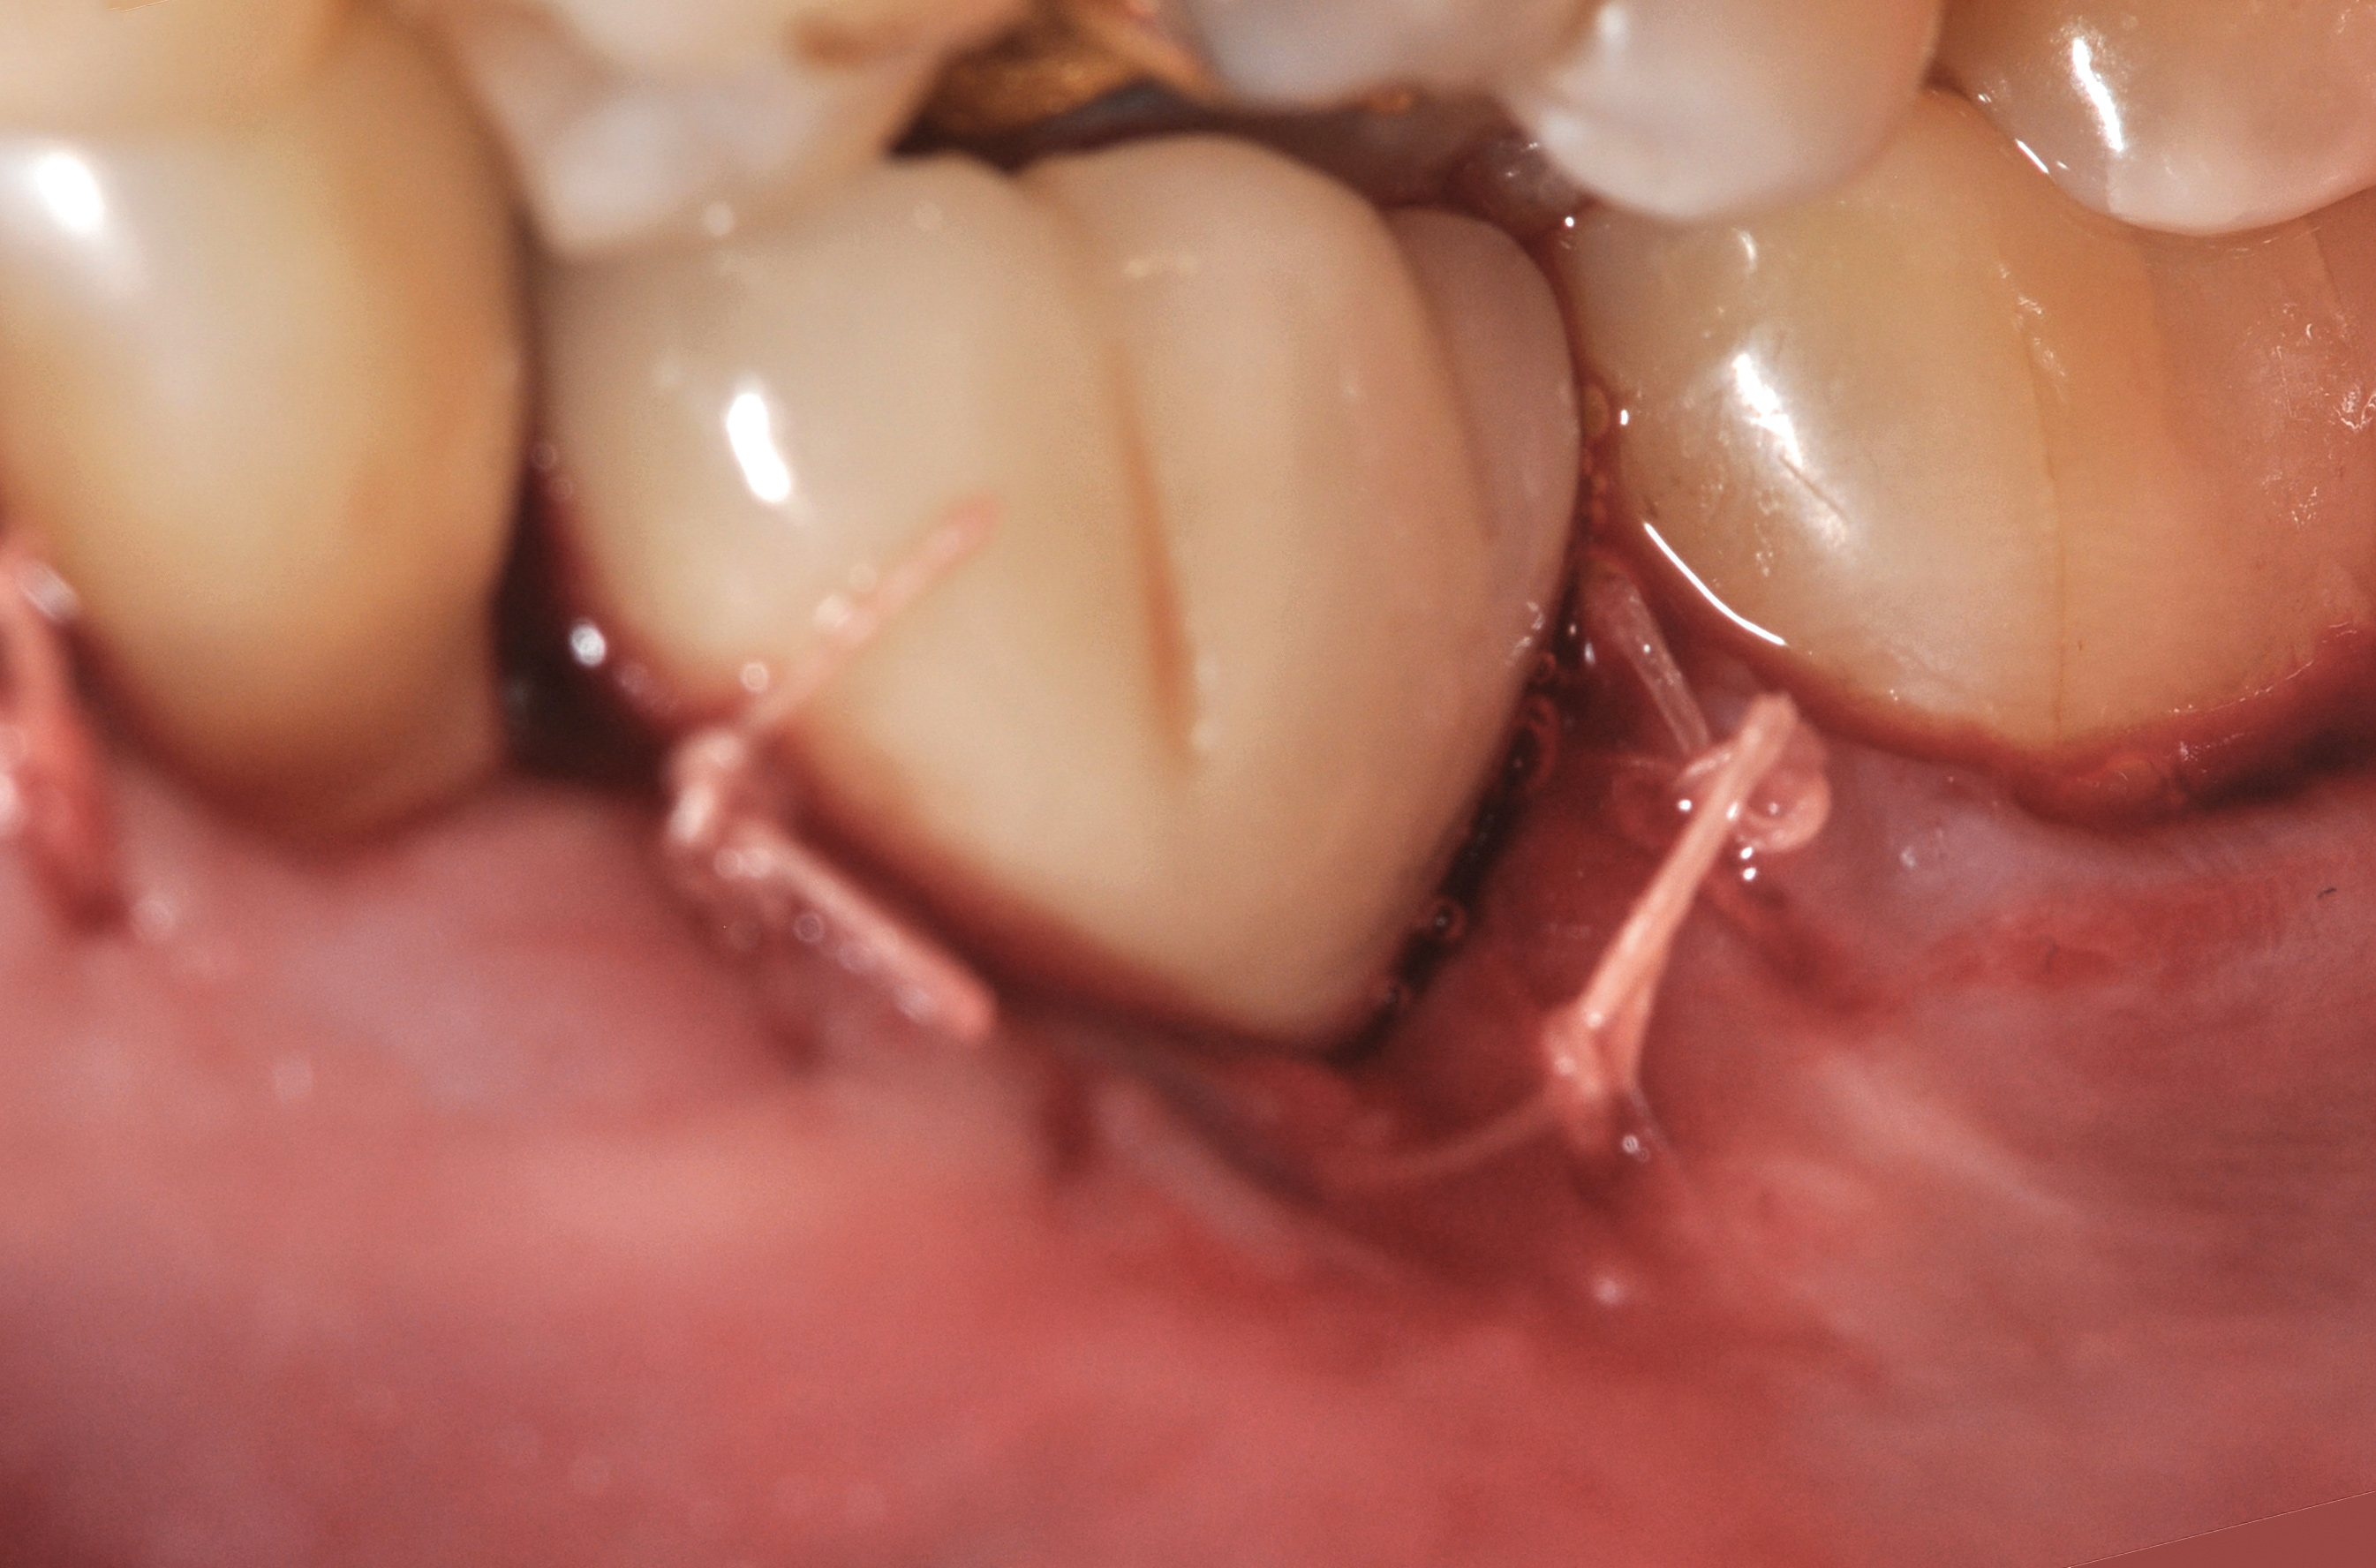

A surgical flap procedure was performed with the intent of thoroughly debriding the granulomatous tissue from the osseous defect (Figure 18 and Figure 19), mechanically and chemically detoxifying the surface of the implant (Figure 20 through Figure 22), and grafting the infrabony component of lesion with bone xenograft (Bio-Oss®, Geistlich Pharma, www.geistlich-na.com) in an attempt to reduce the vertical defect (Figure 23). To concurrently resolve the mucogingival problem, the plan called for placing a dermal allograft (Dermis Allograft, DENTSPLY International, www.dentsply.com) on the buccal (Figure 24) and then replacing the flap (Figure 25).

Fig 18. A full-thickness flap from teeth Nos. 18 to 20 revealed granulomatous tissue in the circumferential defect around implant No. 19.

Fig 19. The circumferential defect was debrided. Note excess cement extending apically from the margin of the crown into the defect; residual cement has been shown to be complicit in the development of peri-implant disease.